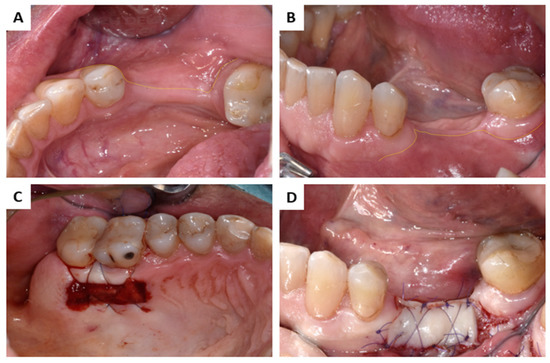

2.2. Interactions in Patients

3.2. Interactions in Patients